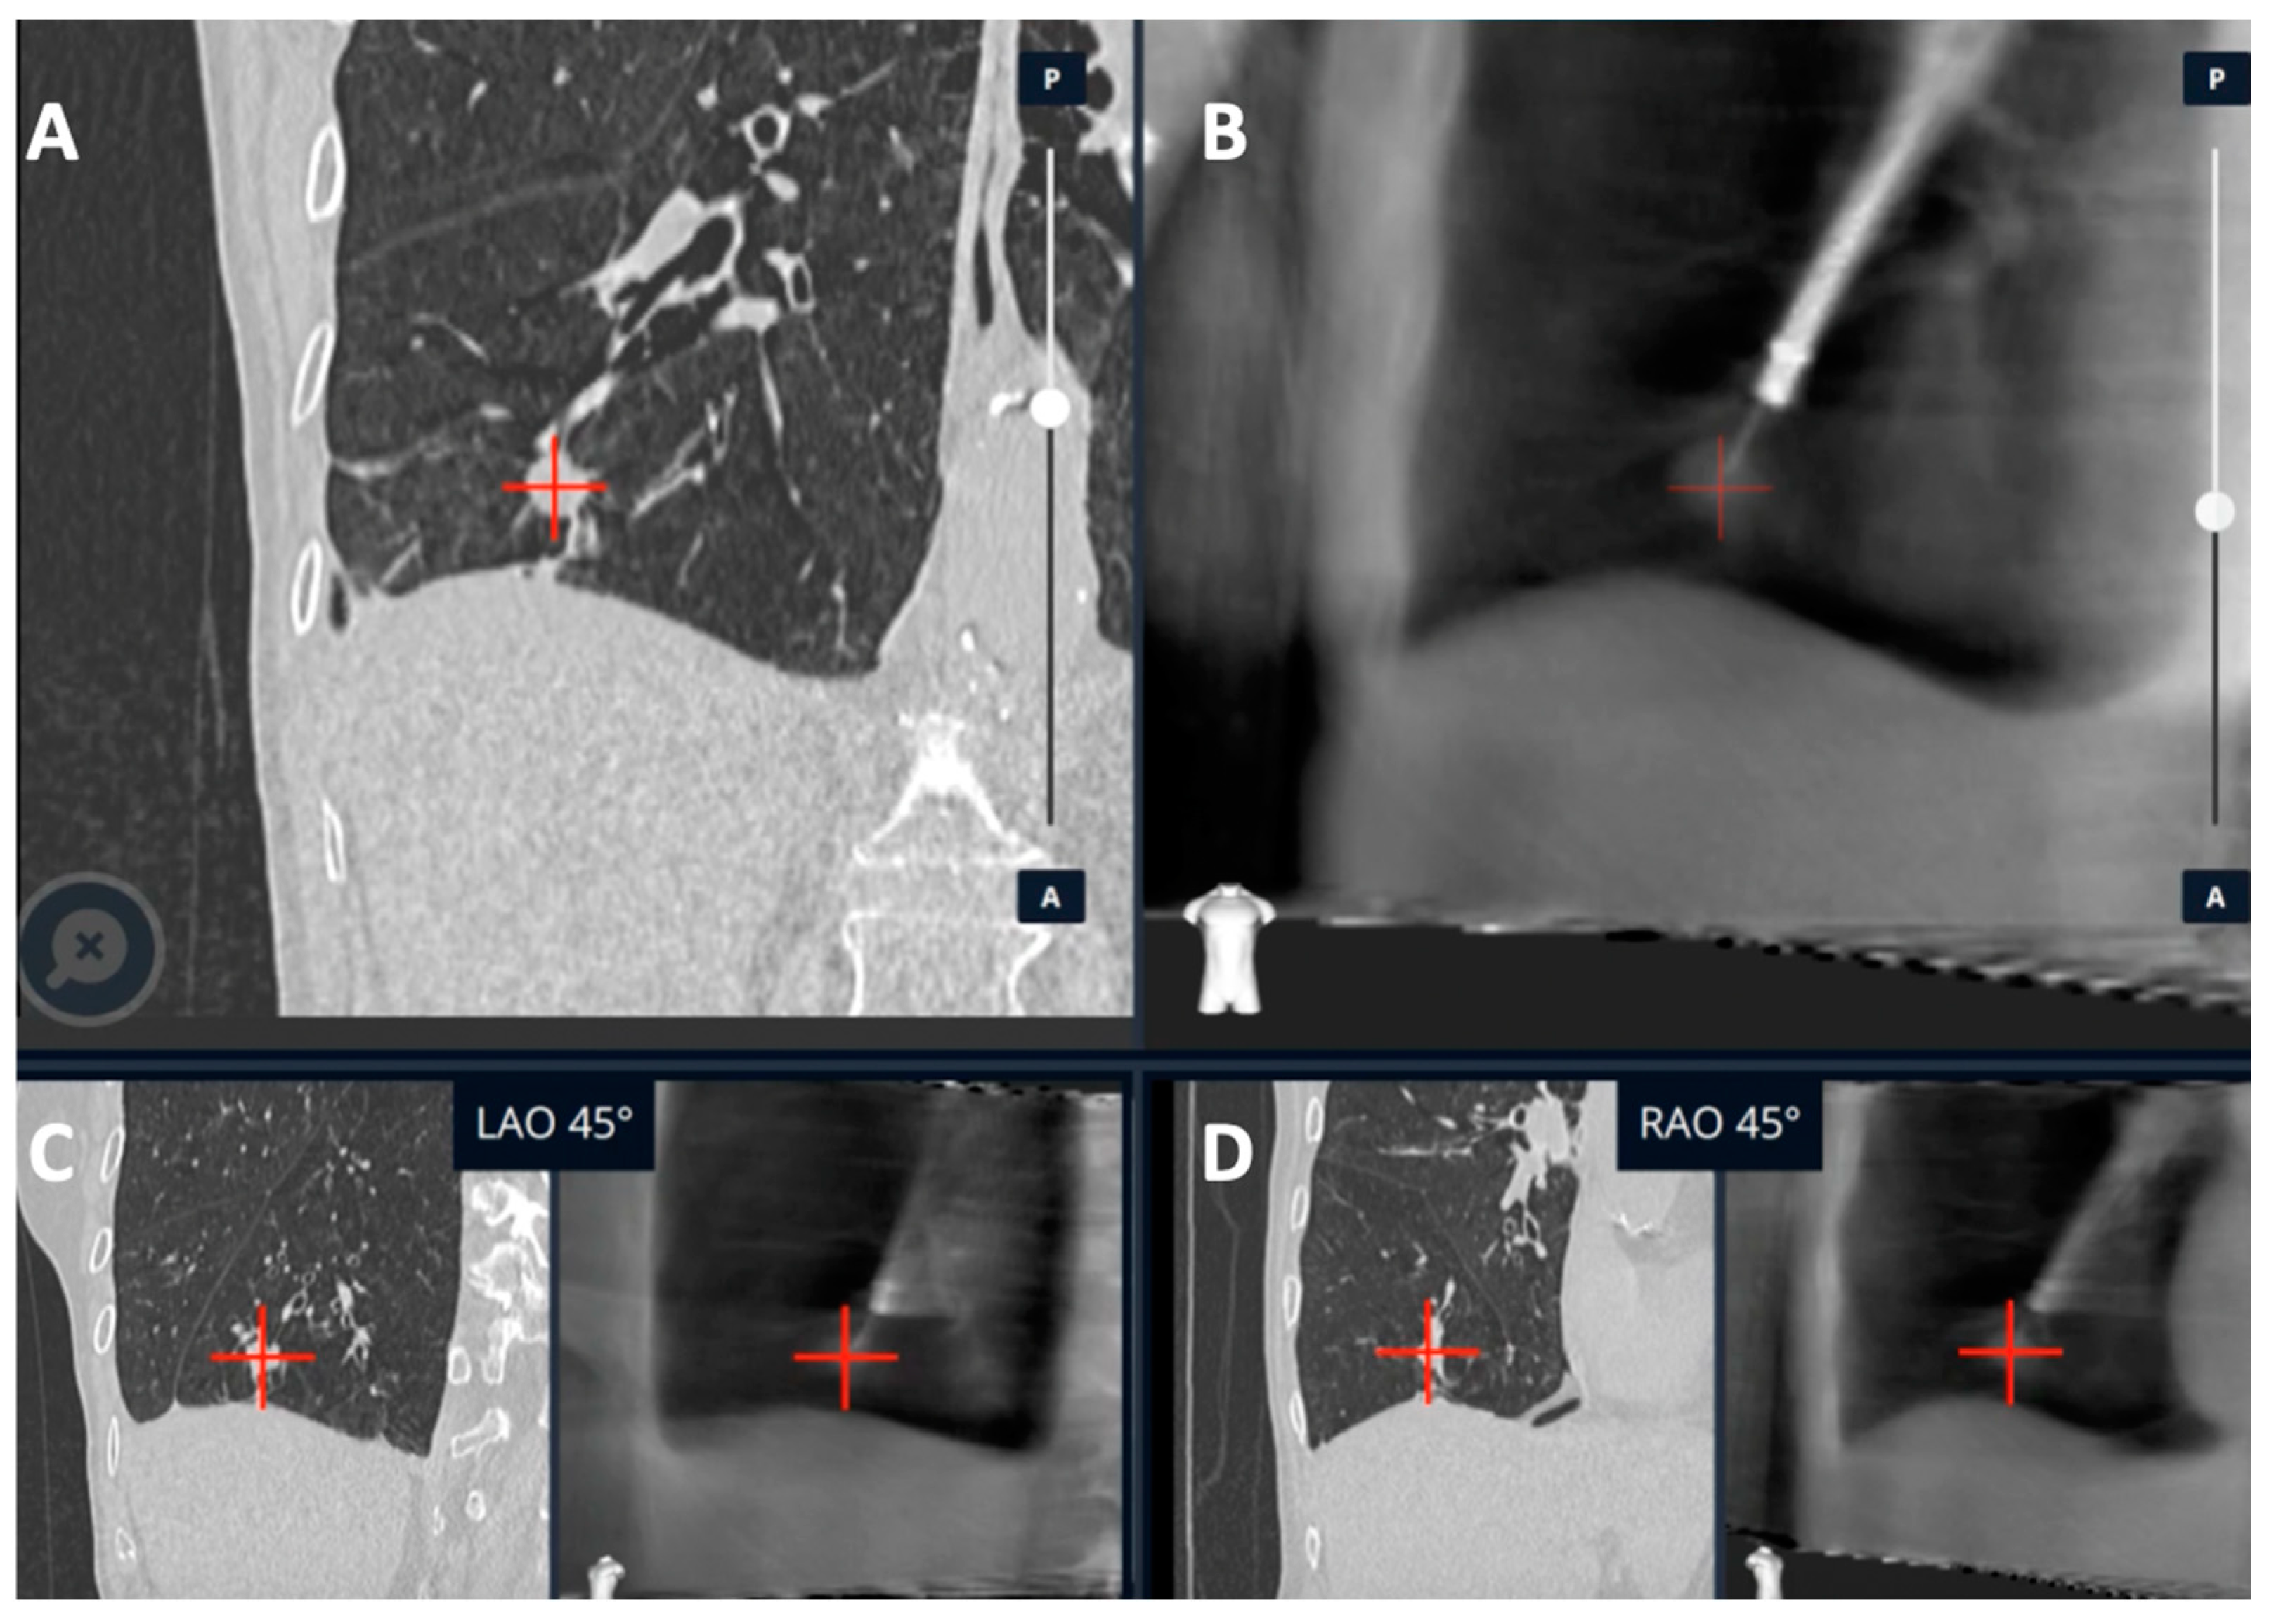

3. Cone-Beam CT

3.1. CBCT with Conventional and Non-RAB Navigation Platforms

3.2. CBCT with RAB Navigational Platforms

- Hedstrom, G.; Wagh, A.A. Combining Real-time 3-D imaging and augmented fluoroscopy with robotic bronchoscopy for the diagnosis of peripheral lung lesions. Chest 2022, 162, A2082. [Google Scholar] [CrossRef]

- Kalchiem-Dekel, O.; Fuentes, P.; Bott, M.J.; Beattie, J.A.; Lee, R.P.; Chawla, M.; Husta, B.C. Multiplanar 3D fluoroscopy redefines tool-lesion relationship during robotic-assisted bronchoscopy. Respirology 2021, 26, 120–123. [Google Scholar] [CrossRef] [PubMed]

| Kalchiem-Dekel et al. [20] | Ion™ robotic platform with CIOS | Robotic platform for navigation with 3D multiplanar fluoroscopy for intra-procedural real-time guidance | 10 lesions | Tool in lesion: 90%. Tool correction in 30% lesions with real-time imaging. DY not reported | - |

| Reisenauer et al. [11] | Ion™ robotic platform with CIOS | Robotic platform for navigation with 3D multiplanar fluoroscopy for intra-procedural real-time guidance | 30 lesions | DYi: 93%. Average divergence: 10 mm in upper lobe 20 mm in lower lobe | No adverse events |